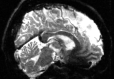

Refer to captionRefer to captionRefer to caption+vsubscript𝑣\mathcal{I}_{+v}inputRefer to captionRefer to captionRefer to captionPyHySCO (LBFGS)Refer to captionRefer to captionRefer to captionPyHySCO (GN)Refer to captionRefer to captionRefer to captionPyHySCO (ADMM)Refer to captionRefer to captionRefer to captionvsubscript𝑣\mathcal{I}_{-v}Refer to captionRefer to captionRefer to captionRefer to captionRefer to captionRefer to captionRefer to captionRefer to captionRefer to captionRefer to captionRefer to captionRefer to caption|+vv|subscript𝑣subscript𝑣|\mathcal{I}_{+v}-\mathcal{I}_{-v}|Refer to captionRefer to captionRefer to captionRefer to captionRefer to captionRefer to captionRefer to captionRefer to captionRefer to captionRefer to captionRefer to captionRefer to captionfield map 𝐛𝐛\mathbf{b}Refer to captionRefer to captionRefer to captionRefer to captionRefer to captionRefer to captionRefer to captionRefer to captionRefer to caption+vsubscript𝑣\mathcal{I}_{+v}TOPUPRefer to captionRefer to captionRefer to captionHySCORefer to captionRefer to captionRefer to captionvsubscript𝑣\mathcal{I}_{-v}Refer to captionRefer to captionRefer to captionRefer to captionRefer to captionRefer to caption|+vv|subscript𝑣subscript𝑣|\mathcal{I}_{+v}-\mathcal{I}_{-v}|Refer to captionRefer to captionRefer to captionRefer to captionRefer to captionRefer to captionfield map 𝐛𝐛\mathbf{b}Refer to captionRefer to captionRefer to caption